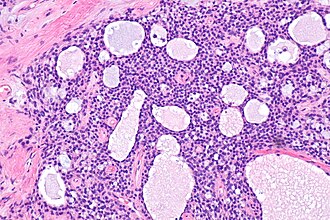

Microcystic stromal tumour of ovary. H&E stain. | |

| LM | microscopic cysts alternating with solid cellular regions, hyalinized fibrous stroma |

- Microcysts alternating with solid cellular regions.

- Hyalinized fibrous stroma.